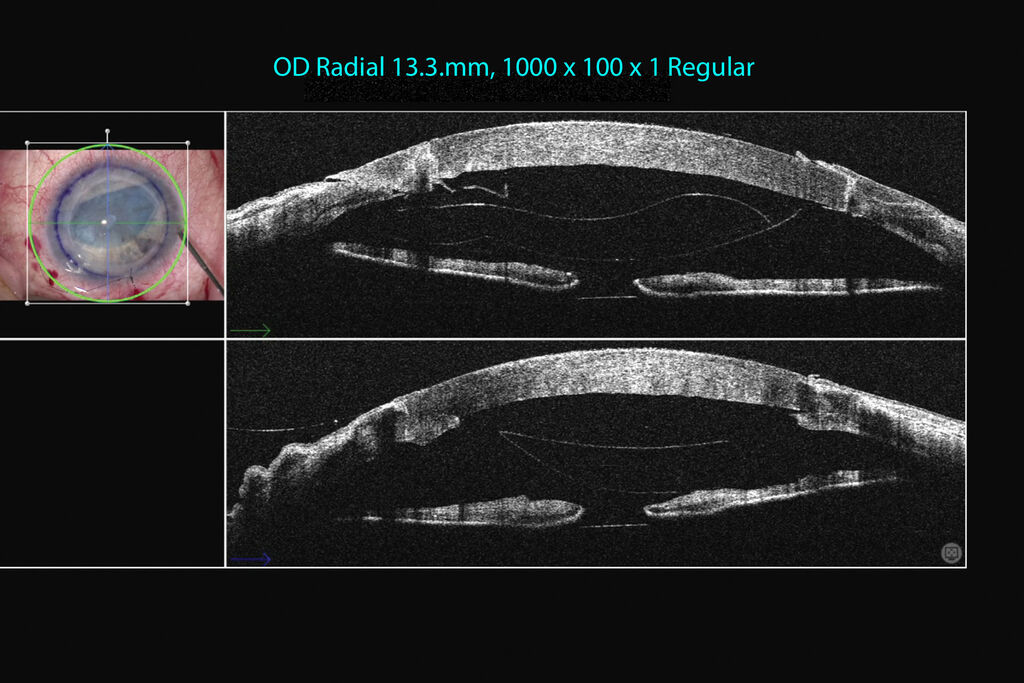

Cataract Incision Analysis Using EnFocus Intraoperative OCT Science Leica Enfocus Enfocus oct medical equipment pdf manual download. Widely recognized for optical precision and innovative technology, leica microsystems is one of the market leaders in. See the details you are looking for with high. I need assistance/training in how to. The optimized enfocus design lets you work in a more comfortable and relaxed posture at the microscope. View and download leica. Leica Enfocus.